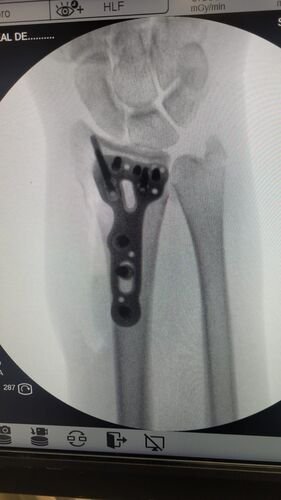

Meu nome e Isabella, mais conhecida como Snow, eu estava andando de muleta e a borracha dela saiu e eu tenho problema de equilibrio devido ao meu femur, bati o osso e piorou a situação, tive o radio do braço afetado e colocaram pino e deram um jeito de reverter porque eu ficaria com movimento do braço e mão comprometidos, tive traumatismo craniano porque bati a cabeça, esse ano eu já tinha sofrido um depois de um aparelho de raio x cair na testa mas fiquei sem sequelas na cabeça. Bom como muitos que me acompanham eu tenho uma condição rara entre mulheres que eu tenho os ossos do fêmur necrosados em mais de 75% desde 2022, eu sofri um acidente hoje andando de muleta, machuquei o fêmur, rosto, tivd que operar porque era uma emergência, não tenho muitas fotos pois estava internada mas tentei no SUS e não tinha pino de titânio,meu caso era de extrema urgência, eu to vendendo tudo e abrindo mão ate do meu apartamento pra cobrir a cirurgia e tenho ate final de setembro pra bater pelo menos 20 mil de meta, tenho inúmeras vakinhaa mostrando minha real doença autoimune e uma delas sendo rara que é osteonecrose bilateral do fêmur, o tratamento tá sendo todo particular mesmo sendo paciente do hospital das clínicas, ainda e difícil e nem sempre consigo as coisas, eu tento de todas formas é isso ainda pode me prejudicar na minha carreira, detesto pedir ajuda mas não tenho opção, a comunidade da minha área entre outros interesses sempre me apoiaram e infelizmente veio com humildade e de cabeça baixa pedir ajuda, faz tempo que tento recomeçar minha carreira desde o diagnóstico e nunca desisti dos meus sonhos e cirurgia

Vou deixar imagem atual do acidente abaixo e de algumas vakinhas anteriores